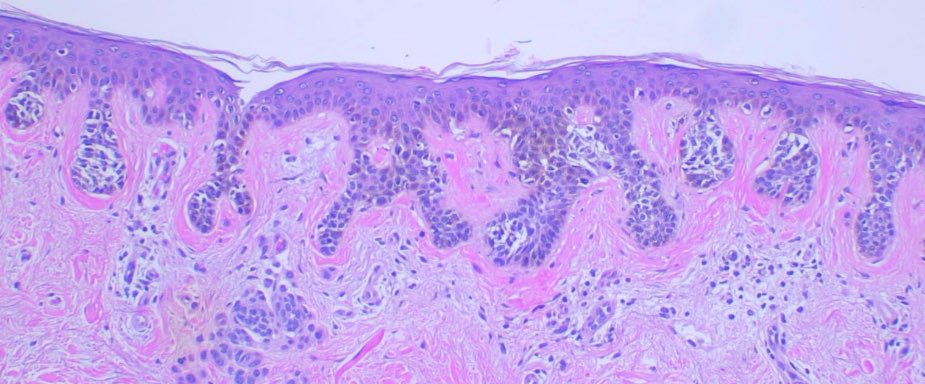

Concentric fibrosis is a histologic feature found in dysplastic nevi, where fibrosis forms a ring-like pattern around a rete ridge #path #dermpath #dermatology #pathology